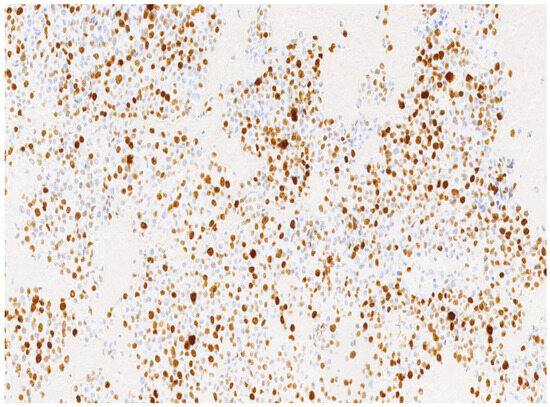

3. Results